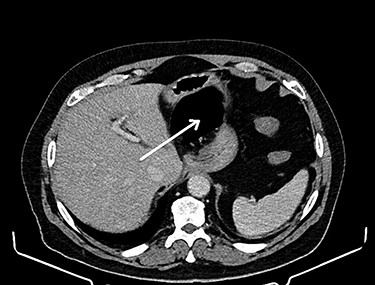

CT of the abdomen is considered the gold standard of the diagnosis of the internal hernia through the foramen of Winslow. The most prominent feature is the presence of intestinal loops between the inferior vena cava and portal vein [4] (see Fig. 1). Another classic feature is the presence of distended intestinal loops posterior to the stomach, which is displaced along with first and second part of the duodenum to the left [5] (see Fig. 2).

Reduction of the hernia could be challenging due to the marked distention of the entrapped intestinal loop (see Fig. 3). Bowel decompression through needle puncture or a small incision was frequently described to facilitate the reduction [7]. Another accepted option is widening the foramen of Winslow to aid reduction using Kocher’s maneuver [8]. The duodenum could be mobilized to the left by incising the peritoneum at its right edge. This technically demanding maneuver is reserved as a last resort. Bowel resection is indicated in case of a non-viable strangulated bowel. On the other hand, viable bowel is frequently reported, where no resection was needed [9]. Right hemicolectomy was described along with caecopexy and narrowing of the foramen Winslow as recurrence prevention maneuvers [7]. These maneuvers are highly debatable due to their added risk of postoperative morbidity in the lack of a hard evidence of recurrence, which remains more of theoretical risk [10].

Herniated caecum and ascending colon through the foramen of Winslow.